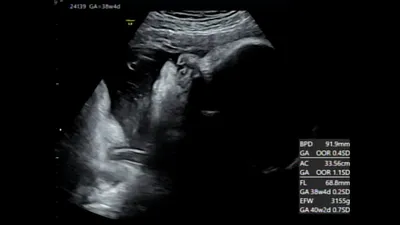

妊娠38週目の赤ちゃんの様子・エコー

妊娠38週頃になると、体の機能の発達はすでに完了し、皮膚が徐々に厚くなってきます。皮下脂肪も増えて、生まれたときと変わらないふっくらした姿です。

この時期の赤ちゃんは、規則正しく寝たり起きたりを繰り返しています。感覚も発達していて、声をかけたり大きな音がしたりすると胎動で反応を見せることもありますよ。

妊娠38週目頃の赤ちゃんの大きさ

受精から:252日~258日目

頭殿長:約49cm

体重:2300g~3300g